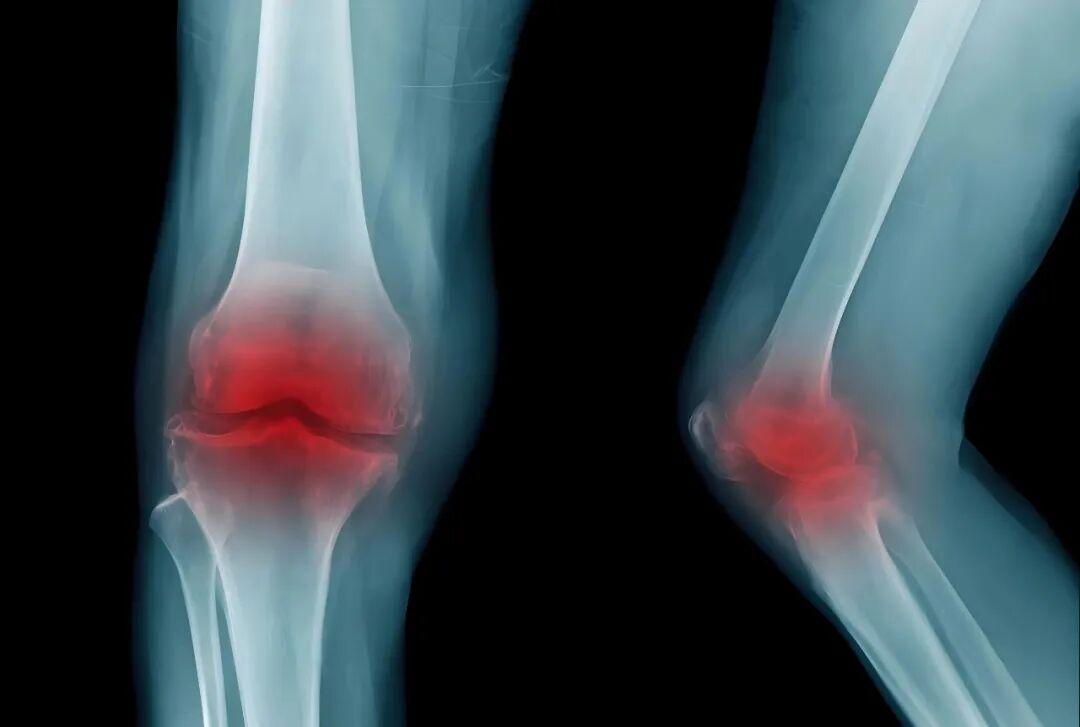

1.膝關(guān)節(jié):作為人體主要承重關(guān)節(jié),磨損概率最高。典型表現(xiàn)為:上樓梯、爬坡時(shí)疼痛加重,平地行走緩解;久坐或晨起后關(guān)節(jié)僵硬,活動(dòng)3-5分鐘后改善;嚴(yán)重時(shí)可能出現(xiàn)關(guān)節(jié)腫脹、活動(dòng)時(shí)彈響明顯。